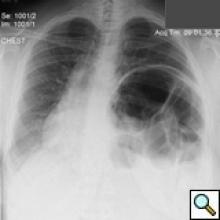

On physical exam she was obese (BMI 34) but in good general condition. There were no abnormalities on the thoracic and abdominal examination other than reduced breath sound at the left lung base. A chest x-ray showed substantial elevation of the left hemidiaphragm (Figure 1). A chest CT showed a massively distended left colon under the left diaphragm (Figure 2). A “sniff test” (fluoroscopic assessment of diaphragmatic function) showed paradoxical motion of the elevated hemidiaphragm.

The patient’s postoperative course was uncomplicated and she was discharged on postoperative day 4. She was seen again in the outpatient clinic approximately a week later and a chest x-ray demonstrated a normal left diaphragm contour (Figure 5).